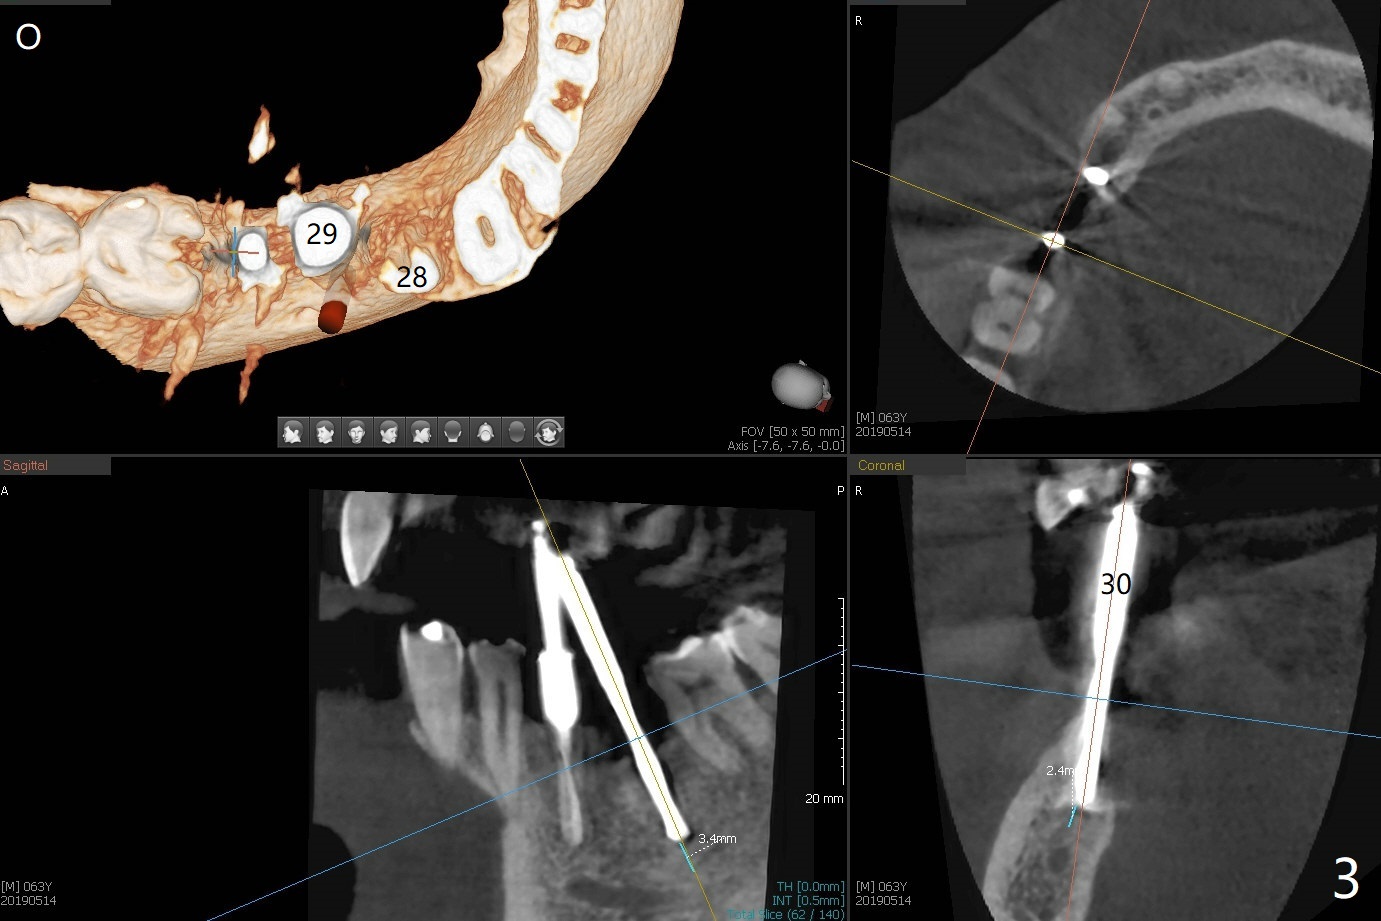

After initial osteotomy using 2.2 mm drill for 10 and 11.5 mm at #29 and 30, respectively, the guide is removed for re-insertion of drills and PA (Fig.1). The osteotomy at #29 is found lingually and in the nonkeratinized gingiva with mild laceration (wish incision to be made before osteotomy); the osteotomy is established a little lingual at #29 (Fig.2) and more or less in the middle of the narrow ridge and #30 (Fig.3). Lindamann bur is used to move #29 osteotomy buccally. A 1.5 mm drill is used to increase the depth free hand before placement of 2.5x10(4) mm 1-piece implants (Fig.4). After adjustment of the implant depth (Fig.5), CT is retaken, which shows proper implant placement (Fig.6,7). Probably due to good oral hygiene, the gingiva around the implants appears to be keratinized 4 months postop (Fig.8). After abutment preparation for margin and parallelism, impression is taken (Fig.9). When the permanent crowns are temporarily cemented, the large gingival embrasure is noted (Fig.10,11). The latter could be reduced by modifying the provisional in the healing stage. In fact the crown at #29 dislodges 2 days post cementation because lingual (Fig.12) and distal (Fig.13) placement. A surgical stent should have been fabricated from RPD for free hand placement!